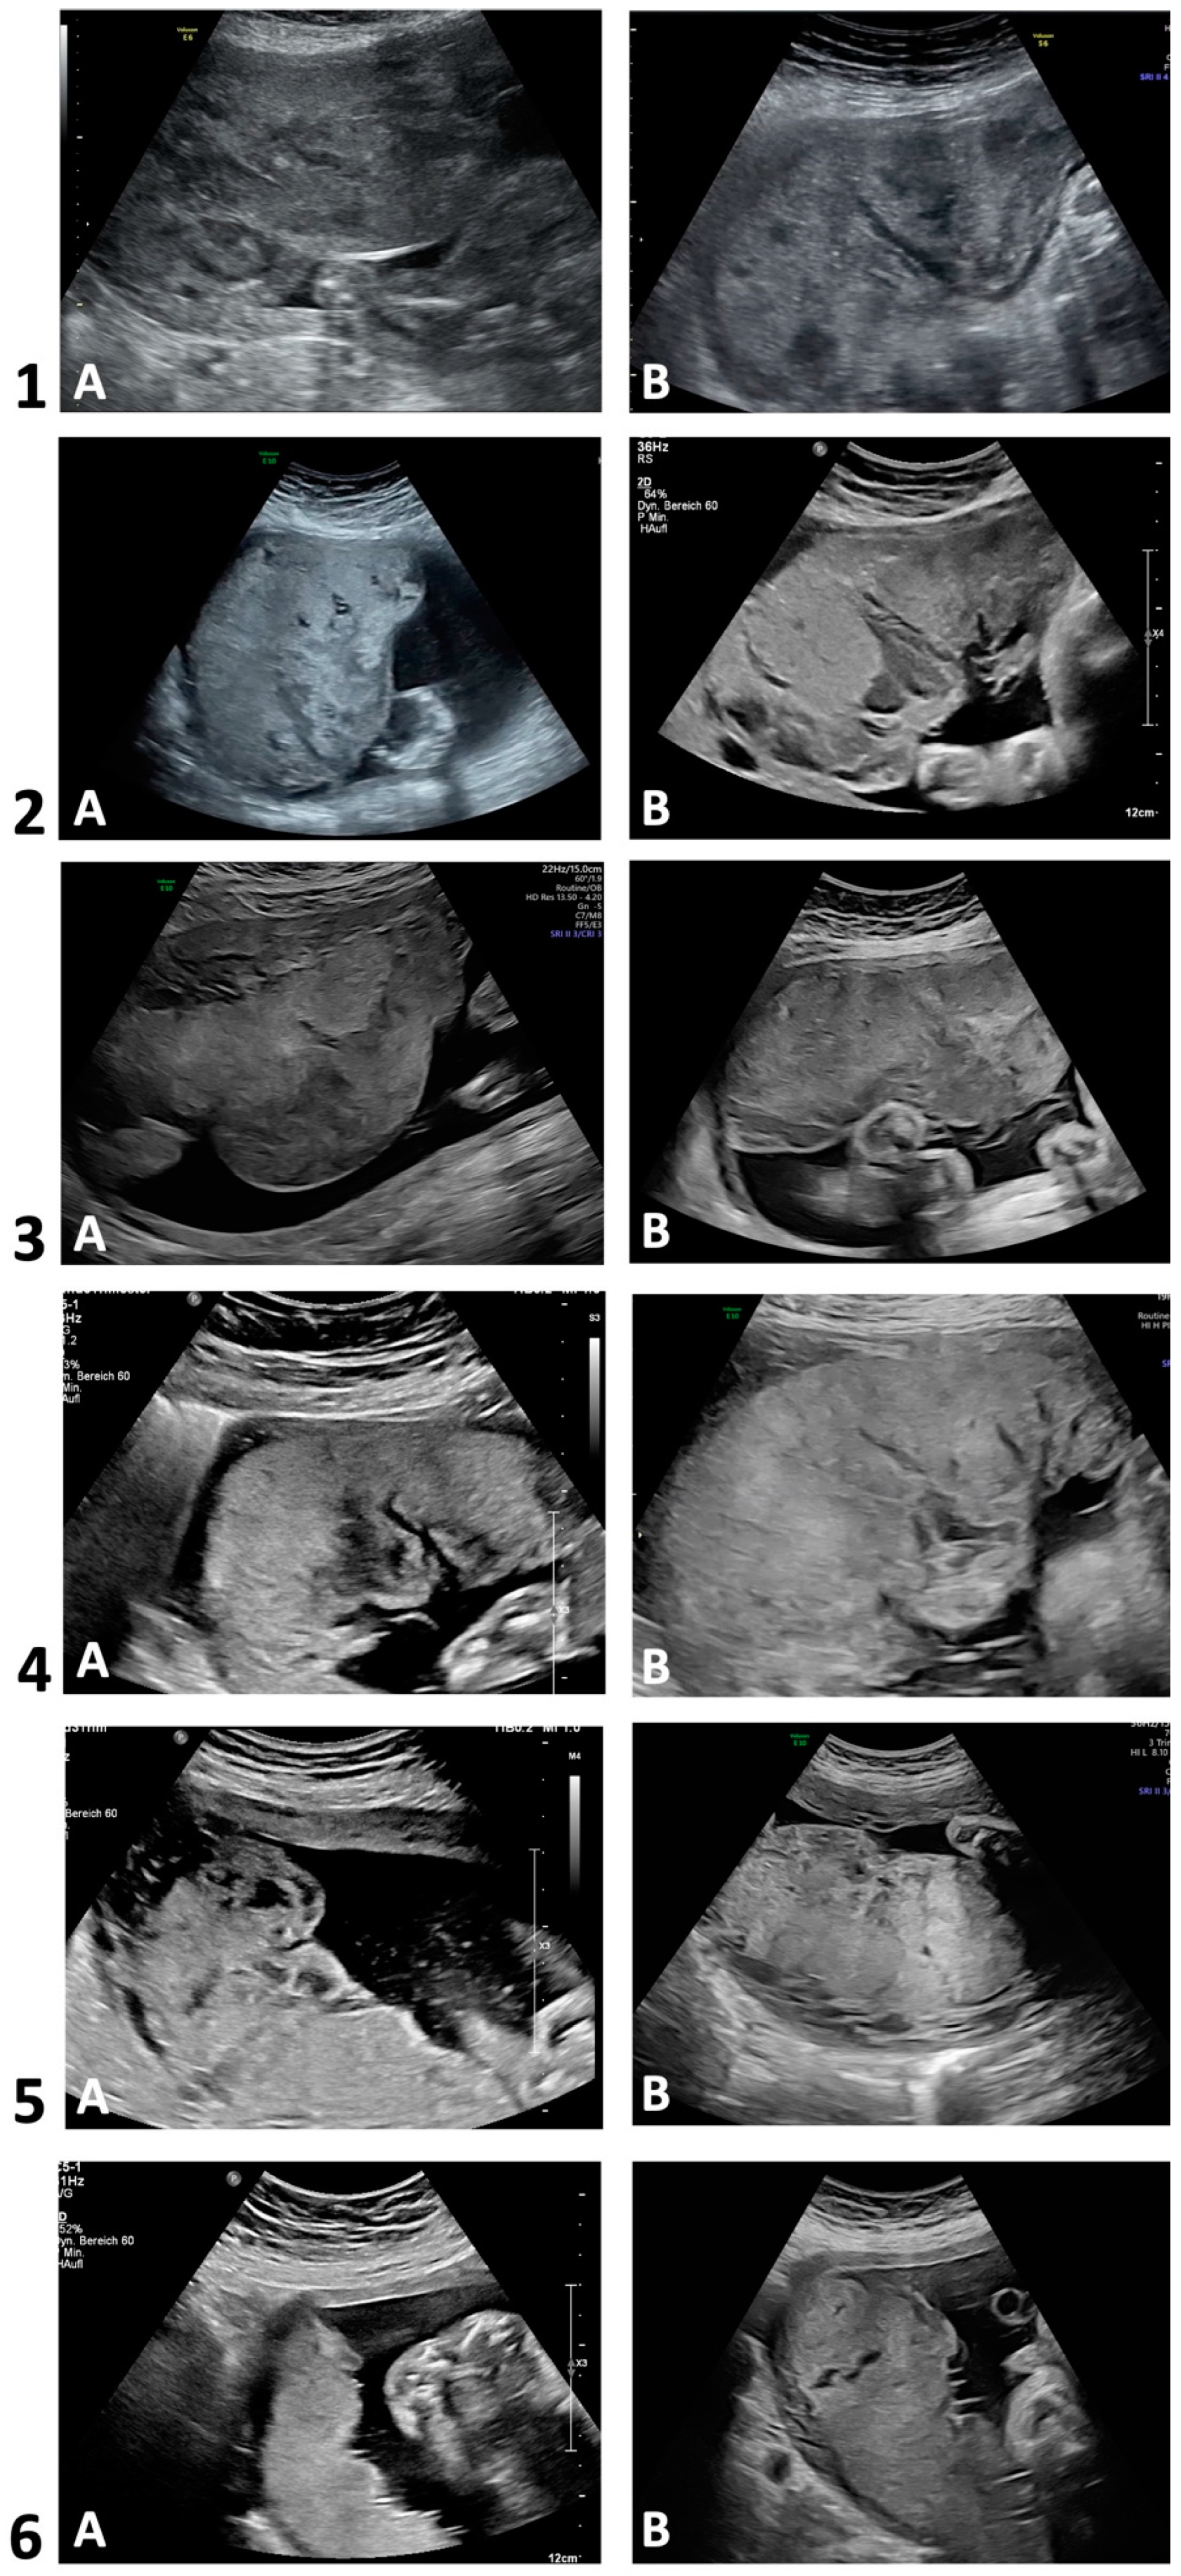

| Ultrasound morphology (see Figure 2) | ||||||

| - First trimester | No data | Normal size and echogenicity | Normal size and echogenicity except for some marginal lakes | No data | Normal size and echogenicity | Normal size and echogenicity |

| - Second trimester | Thickened placental shape; huge lakes distributed throughout the whole placenta (centrolobular, subchorionic and marginal), partially with central maternal clots (jelly-like appearance) | Thickened placental shape; huge lakes distributed throughout the whole placenta (centrolobular, subchorionic and marginal), (jelly-like appearance) | Thickened placental shape; huge lakes (subchorionic and marginal), (jelly-like appearance) | Thickened placental shape; huge lakes (subchorionic and marginal), (jelly-like appearance) | Thickened placental shape; some lakes (centrolobular, subchorionic and marginal), scattered intraplacental calcifications | Normal size and echogenicity |

| - Third trimester | Thickened placental shape; huge lakes distributed throughout the whole placenta (centrolobular, subchorionic), (jelly-like appearance) | Thickened placental shape; huge lakes distributed throughout the whole placenta (centrolobular, subchorionic and marginal), (jelly-like appearance) | Thickened placental shape; huge lakes (centrolobular, subchorionic and marginal), (jelly-like appearance) | Thickened placental shape; huge lakes (subchorionic and marginal), (jelly-like appearance) | Thickened placental shape; extensive lakes (centrolobular, subchorionic and marginal), scattered intraplacental calcifications (jelly-like appearance) | Normal echogenicity; only a few small centrolobular lakes with peripheral echogenicity |